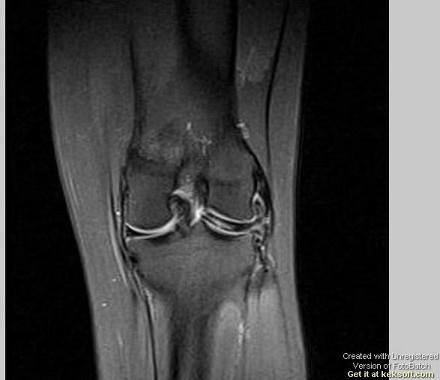

问题 男,16岁,左膝关节有过外伤,现肿痛,有膝关节弹响,请结合MRI检查,选出最可能的诊断 ( )

选项 A、关节结核 B、风湿关节炎 C、滑膜炎 D、半月板撕裂 E、化脓性关节炎

答案 D